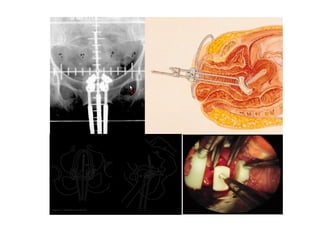

Applicator of ICRT

Intracavitary insertion (ICRT)